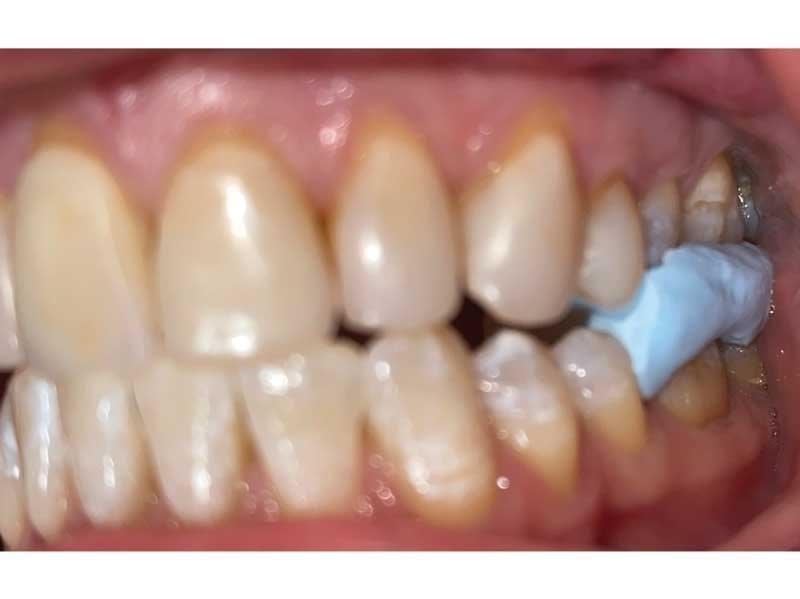

Figs. 5 and 6 show how Lorraine looked in the TENS bite position: The posterior opens and she positions forward and down.

Fig. 5

Dental Occlusion

Fig. 6